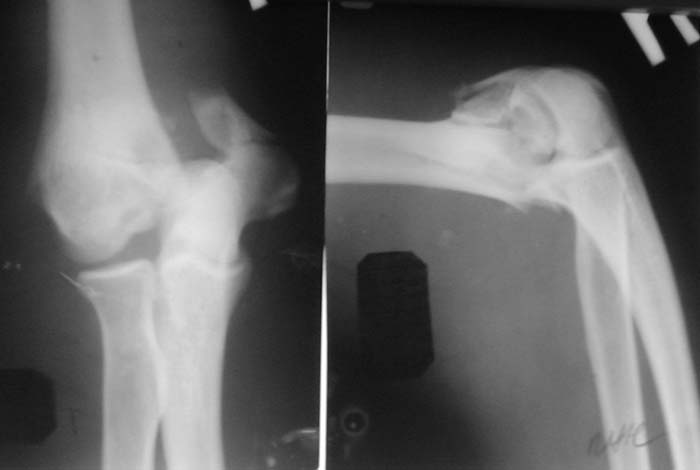

Солидарен с мнением обоих Александров (Челнокова и Рыкова): точную репозицию такого перелома вряд ли удастся выполнить закрыто. Даже во время открытого вмешательства это сделать непросто. Неслучайно предложен костно-пластический доступ с временным отсечением локтевого отростка. И по методу фиксации согласен с Александром Челноковым: 2 пластины. В качестве примера привожу рентгенограммы одного из наших пациентов с аналогичным повреждением.

С уважением, А. Золотов, Приморский край.

Женщина 42 лет, операция через неделю после перелома.

Д-з - открытый перелом мыщелков со смещзением и локтевой кости

без смещения - падение с лошади.

До операции снимки не очень, тем более в гипсе.

Остеосинтез закрытый (если так можно выразиться), т.е. без

разрезов. Длительность операции - около 1,5 часа со студентом.

6 щелчков ЭОПом.